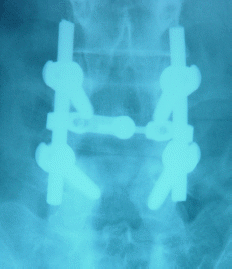

26-APRIL-2007 HANAA KHADER ABBAS 46 YEARS POSTDISCECTOMY III DEGREE SPONDYLOLISTHESIS L4-5 WITH AGONIZING SCIATICA AND WEAK BOTH FEET.

The patient came to the clinic 23-April with agonizing bilateral sciatica and severe weak both feet with inability to walk more than 100 meters.

The patient was operated elsewhere 22-May-2006 for PLD L4-5 with subsequent deterioration of her condition.

MRI done 26-January-2007 with LSS X-ray confirmed the presence of III degree spondylolisthesis L4-5 with complete absence of the isthmi.

On examination: the patient had exaggerated scoliotic stance with SLRS 40 degrees both sides with more pain in the right. The right foot dorsi and planterflexion were 3/5 and the left 4/5. There was hypalgesia of the right L5 and S1 territories.

Skeletonization of the lateral masses of L5-S1 both sides and the L4-5 respectively. There were no lateral masses. The transverse processii were identified and using transpedicular screws 45 mm length and 7.5 mm width with 2 polyaxial type in the upper side and monoaxial in the lower part, transpedicular screw fixation was performed with distraction-reduction with bridge inserted between the 2 rods.

Smooth postoperative recovery with normalization of the power of both feet.

Postoperative Lateral LSS X-ray         Postoperative LSS X-ray AP-view